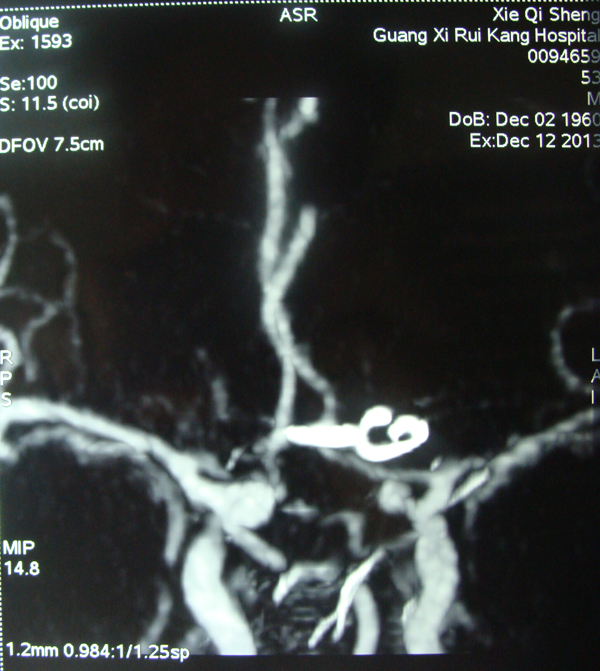

手术后动脉瘤夹。

动脉瘤位置。

前交通动脉位置